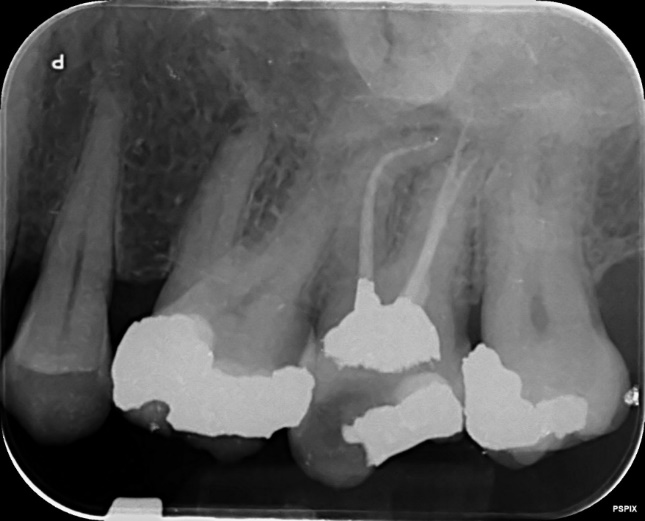

Upper Premolar and Molar root canal treatment and restoration